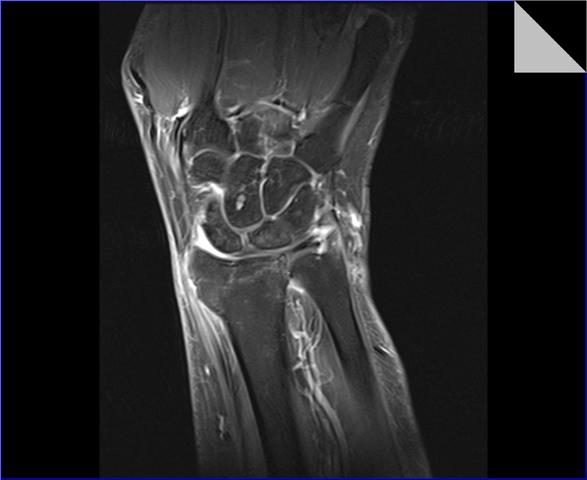

Und außerdem: Die Spulen, die das Bild machen, sind in der Röhre verbaut. Die müssen ja auch irgendwie nah ans Handgelenk rankommen, um scharfe Bilder zu liefern. Wäre ja doof, wenn man hinterher nur Matsch auf den Bildern hätte. Dann könnte man sich das ganze Spektakel ja gleich sparen!